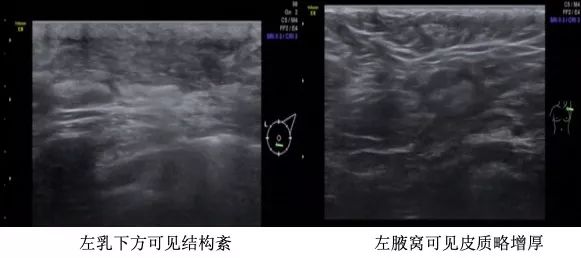

基线影像检查:乳腺MRI(2018年10月31日):左乳下象限肿块,大小6.8cm×4.8cm×6.7cm,BI-RADS:5,左腋窝多发淋巴结转移。乳腺超声(2018年11月5日):左乳肿物,BI-RADS 6;左乳下方象限可见肿物,左侧腋窝可见皮髓质结构消失淋巴结;右乳未及异常。PET-CT(2018年11月1日):左乳癌,左侧腋窝转移淋巴结可能性大。骨(-)、双肺(-)、肝(-)、脑(-)。

乳腺超声(2018年11月5日)